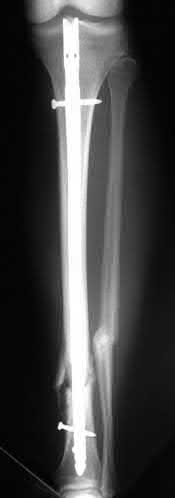

Question 10:

A 45-year-old male sustains a high-energy Schatzker IV tibial plateau fracture. Given the classic displacement pattern of this specific injury, which of the following is the most appropriate surgical approach and fixation strategy to properly neutralize the deforming forces?

Options:

- Anterolateral approach with a single lateral locking plate

- Posteromedial approach with a medial buttress (anti-glide) plate

- Direct midline anterior approach with dual locking plates

- Anterolateral approach with an anterior buttress plate

- Arthroscopic-assisted percutaneous lateral screw fixation

Correct Answer: Posteromedial approach with a medial buttress (anti-glide) plate

Explanation:

A Schatzker IV fracture involves the medial tibial plateau and is typically the result of high-energy varus forces, often combined with an axial load. The primary deforming force drives the medial fragment into varus and posterior subluxation. The biomechanically sound treatment requires a posteromedial approach with a medial buttress (or anti-glide) plate to physically resist the varus and posterior displacement.